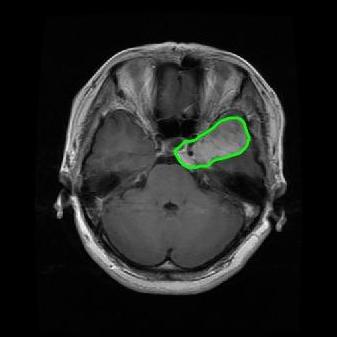

From the above discussions, we have discovered the significant potential of applying Retinex theory to image segmentation and explored its fundamental differences from traditional models. Traditional image segmentation models typically focus on the impact of intensity information on the segmentation results. Therefore, when faced with complex segmentation scenarios, the segmentation results are often affected by lighting, artifacts, and unclear boundaries in the image. As shown in Fig. 1, we present the results of the classical local model LIF [ZHANG20101199] for segmenting brain tumor images along with surrounding tissue edema. The irregular ring-like enhancement caused by the edematous tissue leads to irregular boundaries and low contrast in the images. Consequently, the LIF model can only identify the central necrotic and liquefied regions of the tumor, failing to detect the boundaries and becoming trapped in local minima. In this paper, we draw inspiration from the Retinex theory, which is widely applied in the field of image enhancement. According to Retinex theory, the reflectance component characterizes the intrinsic structural properties of the observed image and preserves texture information independent of illumination variations. By integrating this reflectance component into the level set framework, our model achieves robust segmentation of medical images even under severe intensity inhomogeneity. In addition, a linearized Structural-Prior is proposed to restore intensity consistency and capture local geometric features, thereby improving boundary localization in complex or blurred regions. Furthermore, a relaxed binary level set representation is employed to enhance robustness against noise and to enable accurate tracking of complex contours. Based on these innovations, we propose a novel variational reflectance-based level set model (RefLSM) that simultaneously corrects bias fields and performs segmentation. Experimental results demonstrate that RefLSM significantly outperforms conventional level set methods in both segmentation accuracy and robustness. We present the results of our model segmenting the two brain tumor images mentioned above in Fig. 2.

To address the challenge of segmenting images with severe intensity inhomogeneity, we propose a linearized structural prior that directly operates on the reflectance component . Reflectance-based structural information is more robust to illumination variations and bias field distortions, helping preserve weak edges and subtle anatomical boundaries. As shown in Fig. 2, our method can accurately delineate tumor boundaries and surrounding edema even under severe inhomogeneity, where traditional intensity-based models often fail. The proposed prior aligns smoothed reflectance gradients with data-driven directions, enhancing inter-region contrast, preserving weak edges, and stabilizing the evolution of . Formally, we define the linear structure operator as the gradient field of the smoothed reflectance:

Fig. 4 displays the visual comparison results for segmenting eight brain tumor MR images between the RefLSM and three representative models: the RESLS [8765635], ALF[MA2019201], and L1 model[LIU2019193]. These images exhibit severe intensity inhomogeneity and noise attributable to inconsistent bias field and imaging equipment. The initial level set function (LSF) initialization was consistent across all models, as shown in Fig. 4 (a), which illustrates the initial placement of the zero level contour. For visual clarity, we included the ground truth in Fig. 4 (f). The segmentation outcomes from the RESLS, ALF, and L1 methods are presented in Fig. 4 (b), (c), and (d), respectively.

It is evident from the first and last columns of Fig. 4 (b) that the ALF model tends to become trapped in local minima under severe intensity inhomogeneity. Furthermore, segmentation results presented in the columns 1-4 of Fig. 4 (b) and (c) reveal that both the ALF and L1 models mistakenly segment small isolated or irrelevant regions due to the effects of irregular intensity patterns. Additionally, when weak boundaries are present, as seen in the 1st and 3rd columns of Fig. 4, the RESLS, ALF, and L1 methods fail to accurately identify object boundaries. Consequently, the zero level contours of these models deviate significantly from the objects throughout the level set evolution, causing drastic misalignment after further iterations.

In stark contrast, our proposed method exhibits greater robustness against images exhibiting severe intensity inhomogeneity and weak boundaries. The proposed prior constraint term effectively corrects for intensity inhomogeneity, while the proposed binary level set adeptly reduces noise during the segmentation process.

Overall, these findings demonstrate that the segmentation outcomes produced by our model are more accurate. Besides visual assessment, we calculate the Dice and Precision values of evaluated models for brain tumor segmentation in table 1. Based on these results, we draw a boxplot with scatterplot overlay, as shown in Fig. 6, which displays the data distribution and facilitates comparison of different models’ performance across various brain tumor MR images. We analyze the maximum, median, and minimum, which correspond to the best, median segmentation results, and worst segmentation results, respectively. It is clear that the RefLSM achieves more accurate segmentation results compared to the other models. Moreover, the smaller range of the RefLSM in the boxplot indicates robustness and stability to different images of the brain tumor.